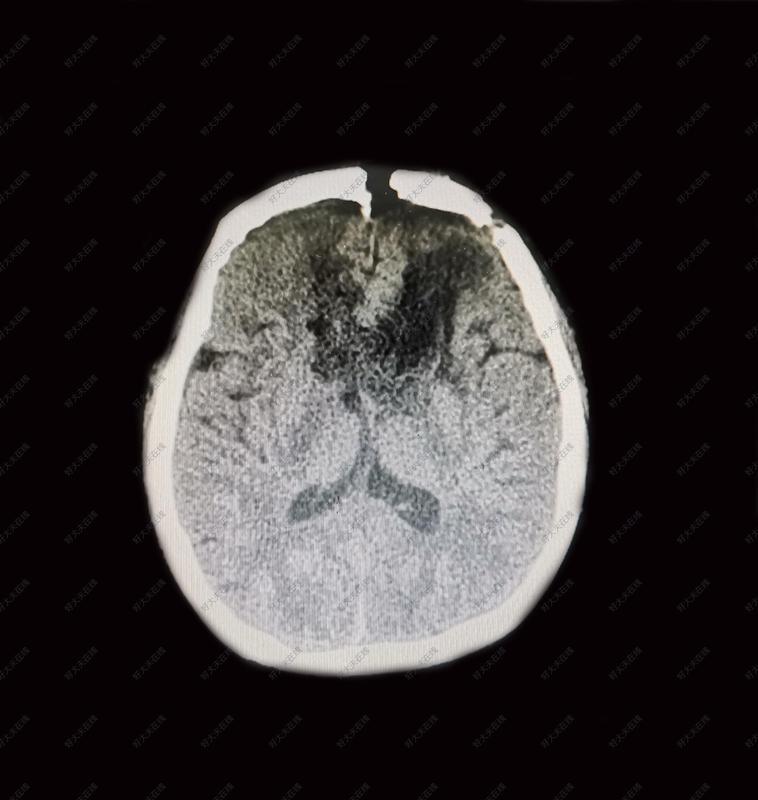

ppt| 累及胼胝体的脑胶质瘤手术切除 - 杨建凯 吕中强 孙国柱 宋剑

图片尺寸960x540